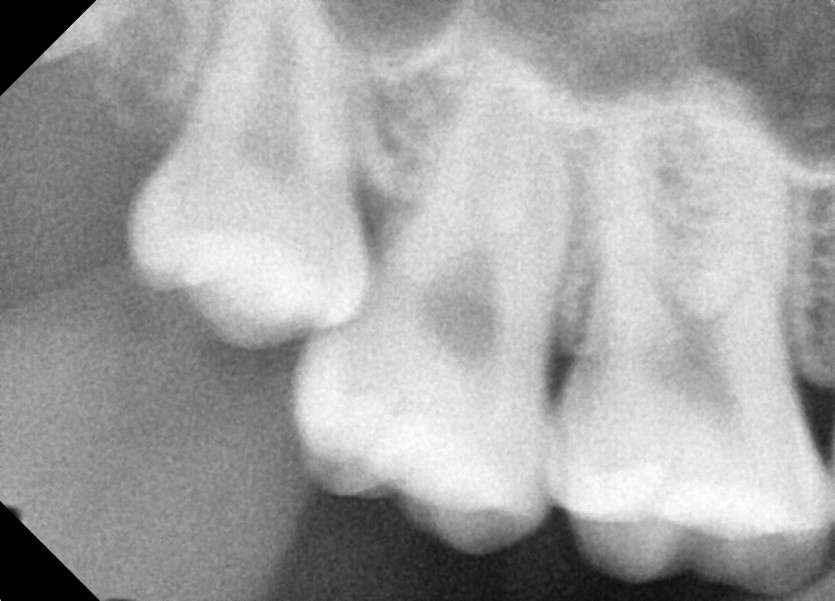

#18,28,38,48 사랑니 발치

구강 외과 전문의가 당일 발치했습니다.